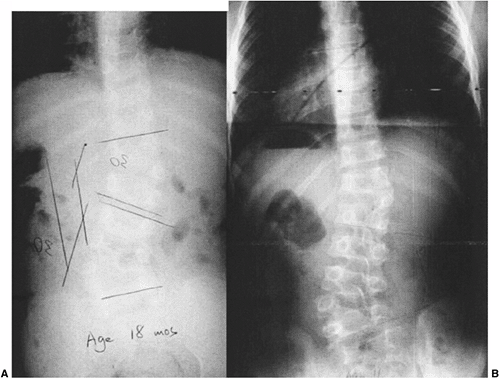

present (Fig. 19.4) (hemimetameric shift), the

congenital scoliosis may be completely unapparent clinically except for

Figure 19.4 Nonprogressive, balanced, double hemivertebrae (“hemimetameric shift”). A: In a child 18 months of age, two hemivertebrae balance each other well. B: At 11 years of age, there has been extensive growth but no worsening of the untreated, balanced deformity.